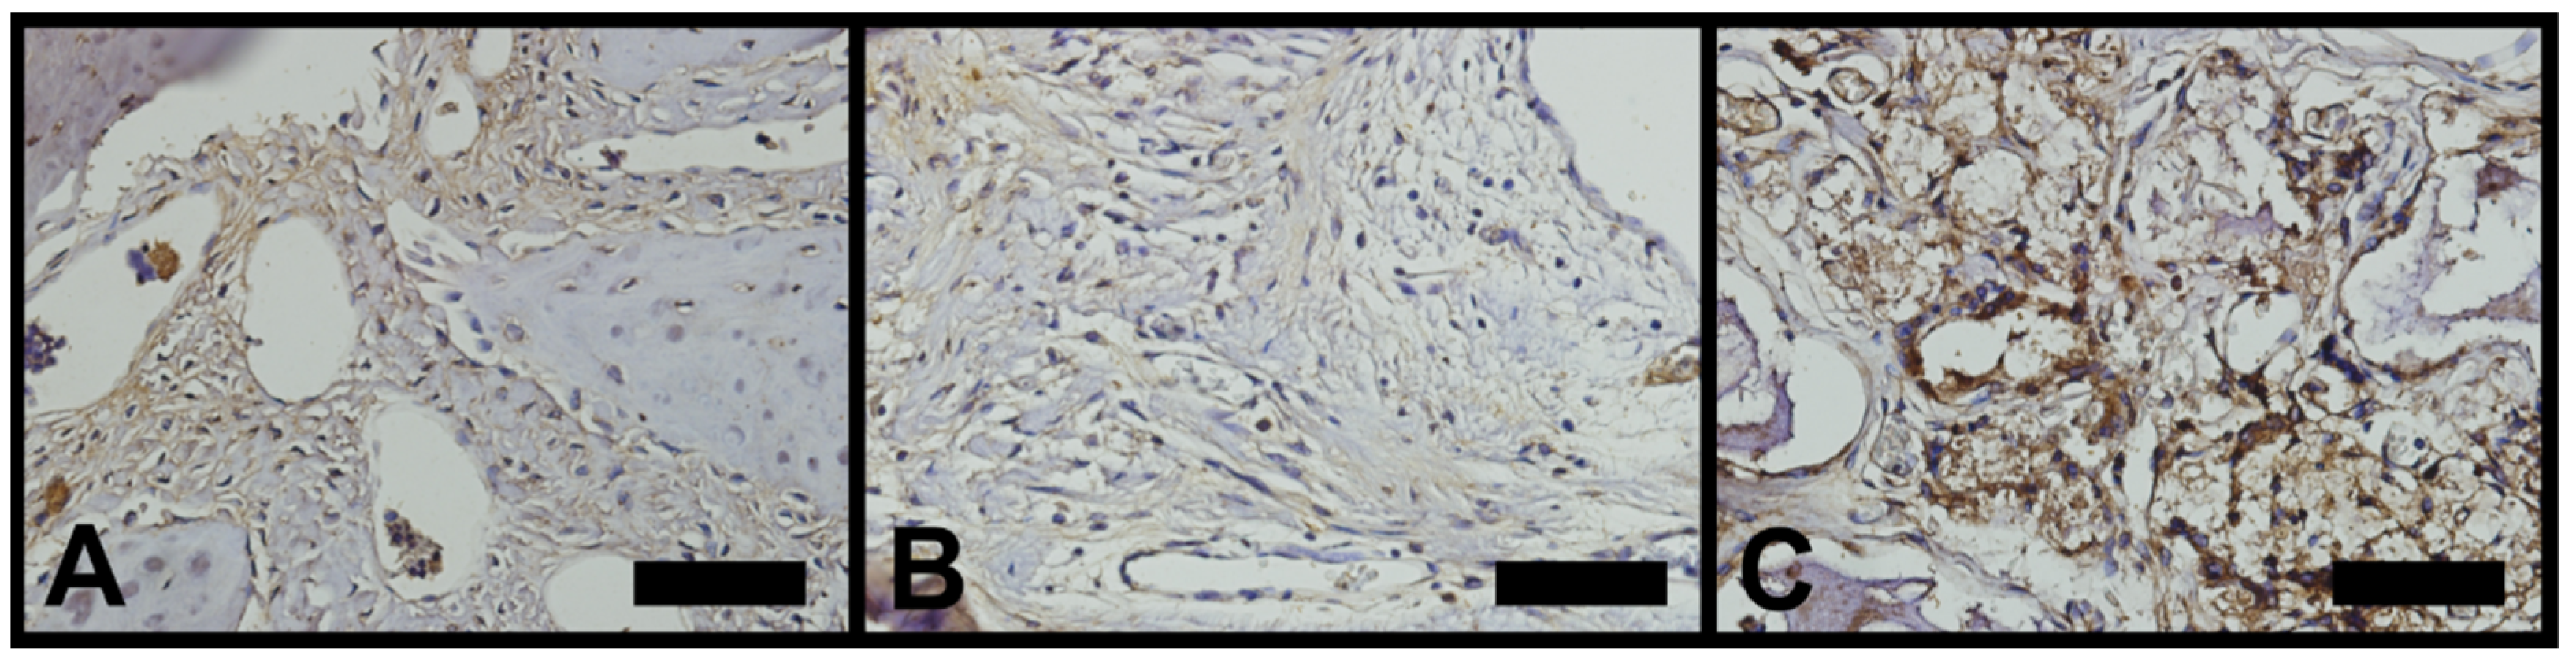

3.3. Vascular Endothelial Growth Factor (VEGF)

- The rate of the protein that promotes the growth of new blood vessels (VEGF) was higher in the nano-hydroxyapatite group than in the other groups.